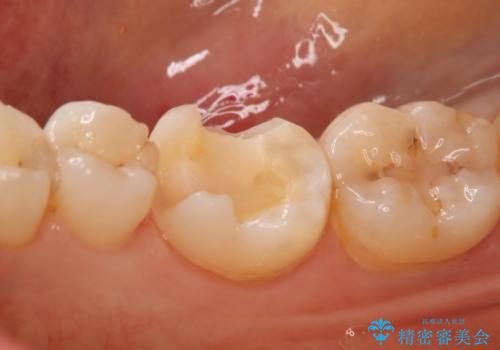

銀の詰め物が取れた セラミックインレー治療

- 右下6番のメタルインレー脱離のため来院。

セラミックの治療を希望されたため切削量を考慮し、セラミックインレーでの治療を選択しました。

う蝕が深くまで進行していたので、CRで裏層した上で形成・印象をしています。